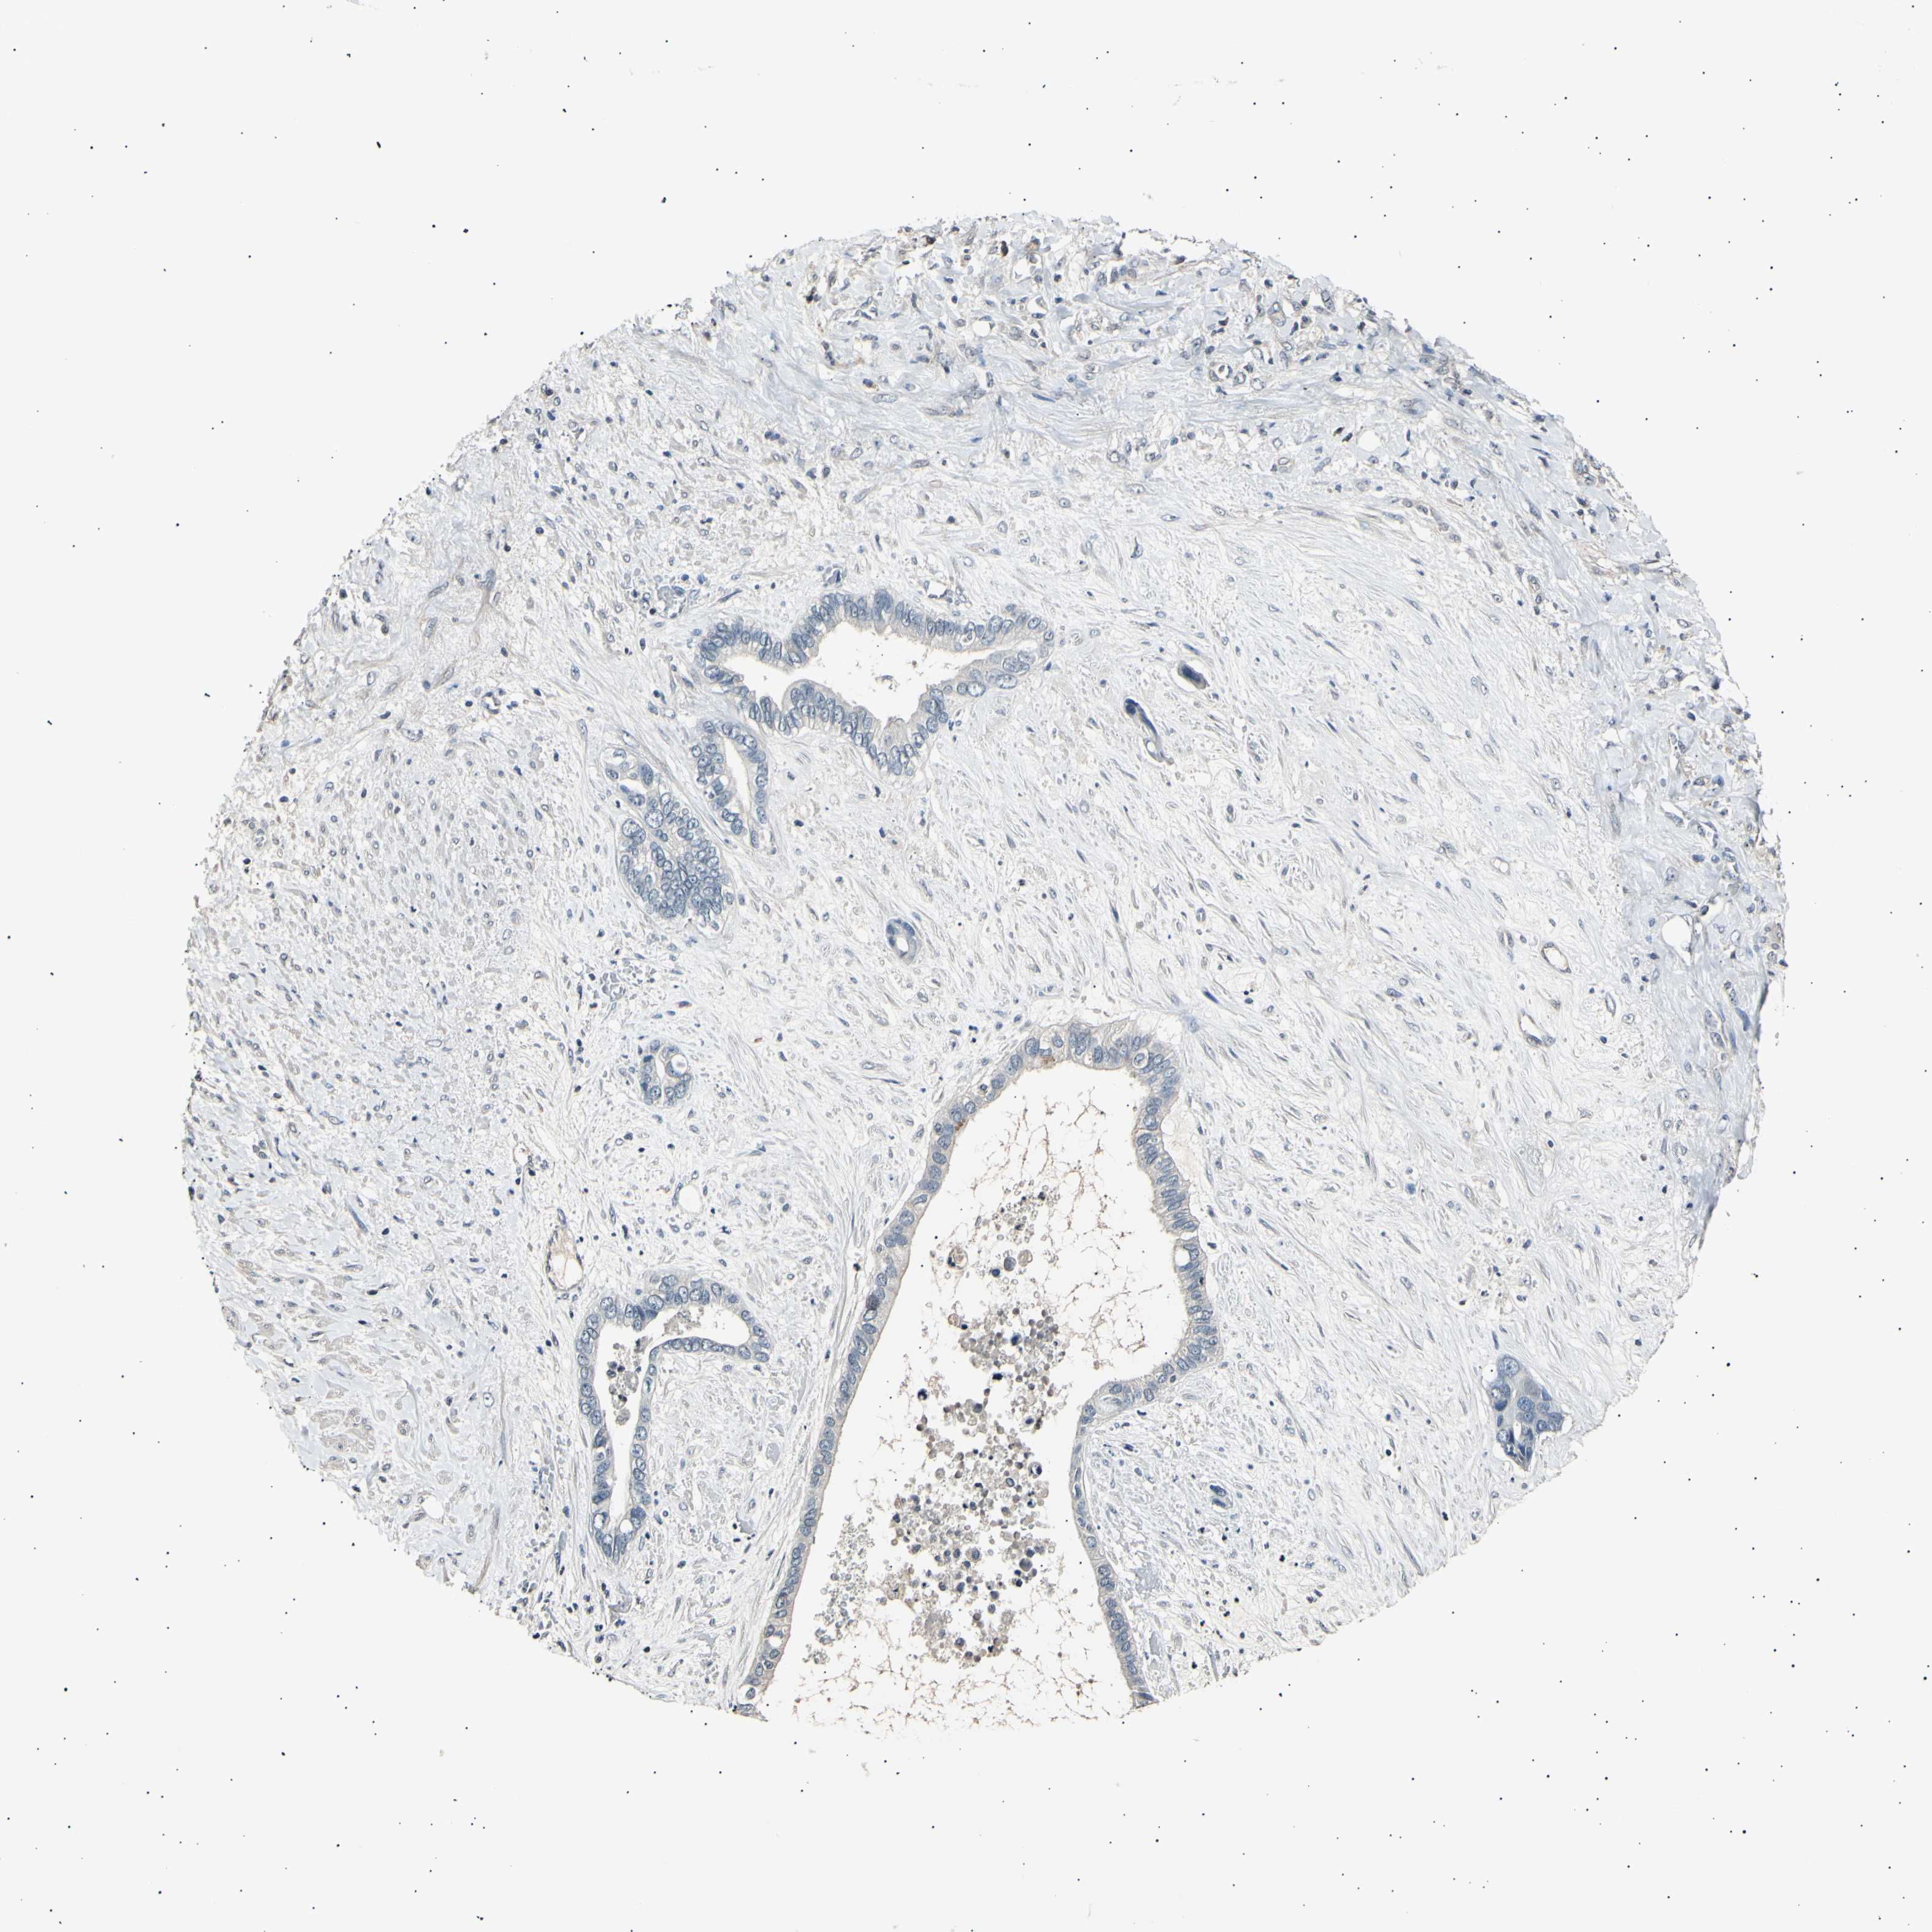

LIVER CANCER - Protein expressioni

A mouse-over function shows sample information and annotation data. Click on an image to view it in a full screen mode. Samples can be filtered based on level of antibody staining by selecting one or several of the following categories: high, medium, low and not detected. The assay and annotation is described here.

Note that samples used for immunohistochemistry by the Human Protein Atlas do not correspond to samples in the TCGA dataset.

Antibody stainingi

Antibody staining in the annotated cell types in the current human tissue is reported as not detected, low, medium, or high, based on conventional immunohistochemistry profiling in selected tissues. This score is based on the combination of the staining intensity and fraction of stained cells.

Each image is clickable and will lead to virtual microscopy that enables deeper exploration of all samples and also displays staining intensity scores, fraction scores and subcellular localization as well as patient and tissue information for each sample.

Antibody HPA006456

Antibody CAB009893

Staining

High

Medium

Low

Not detected

Intensity

Strong

Moderate

Weak

Negative

Quantity

>75%

75%-25%

<25%

None

Location

Nuclear

Cytoplasmic/membranous

Cytoplasmic/membranous,nuclear

Carcinoma, Hepatocellular, NOS

Cholangiocarcinoma

Adenocarcinoma, NOS